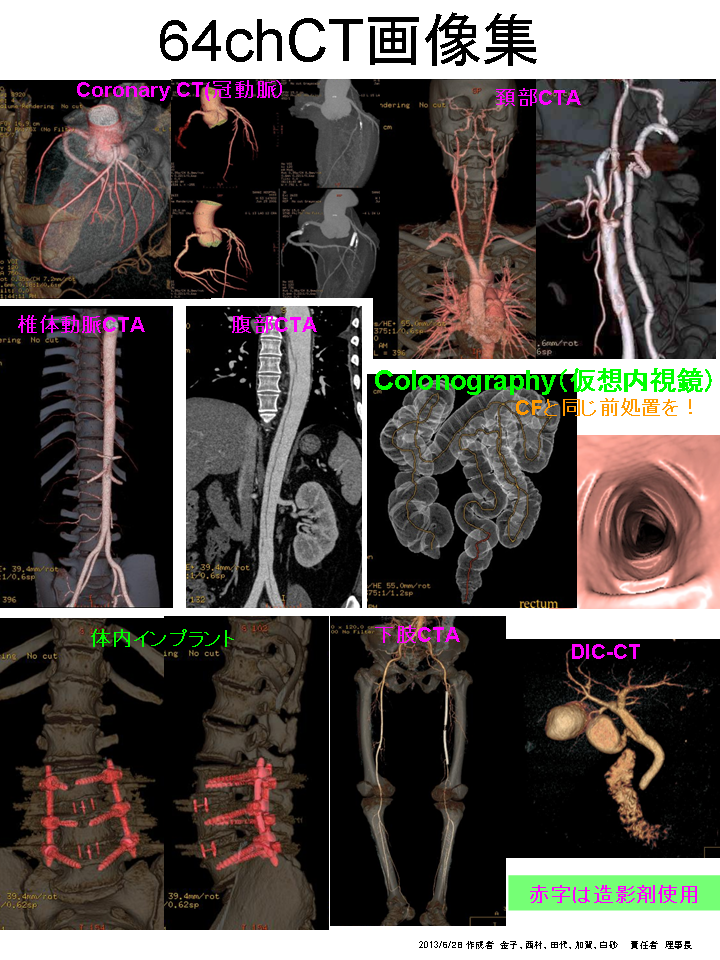

従来のシングルスライスCT、マルチスライスCTと比べ患者さんへの負担が少なく、診断能力の高い超高速ボリュームCT撮影装置。

このボリュームCTにより早期発見から早期治療へつなげることが可能となり、心臓カテーテル検査の代替としても期待されます。

②高速な撮影 : 全身を20秒、0.625mm厚にて撮影可能

③快適度 : 一部の検査では、造影剤の使用量を従来のCTの半分程度に減らすことができます。